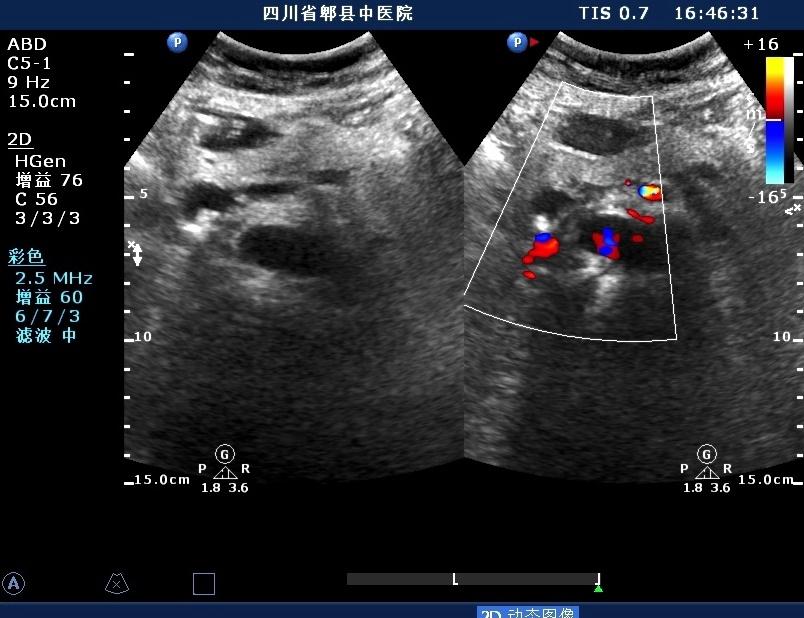

超声如图:胆总管及肝内胆管扩张,呈“平行管征”,胆总管胰腺段可见疏松强回声团堆积,后方可见淡淡声影,左肝外叶胆管内亦可见数个强回声团堆积,后方伴声影。 肝脏及胆总管

胆总管胰腺段结石

左肝内胆管结石